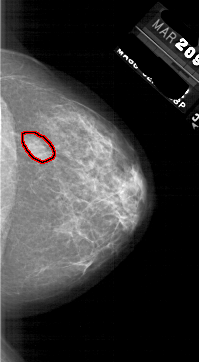

A_1764_1.RIGHT_MLO

RIGHT_CC LINES 5791 PIXELS_PER_LINE 3181 BITS_PER_PIXEL 12 RESOLUTION 43.5 OVERLAY

FILE: A_1764_1.RIGHT_CC.OVERLAY

TOTAL_ABNORMALITIES 1

ABNORMALITY 1

LESION_TYPE MASS SHAPE OVAL MARGINS ILL_DEFINED

ASSESSMENT 4

SUBTLETY 4

PATHOLOGY BENIGN

TOTAL_OUTLINES 1

BOUNDARY